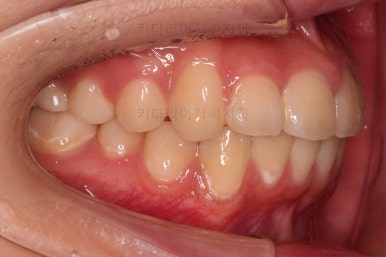

치료 마무리 사진입니다.

연산동치과 전후사진을 비교해 볼게요.

치열이 가지런해지고 교합도 좋아지고 웃는 모습도 매우 좋아졌네요.

비발치 덧니교정이었지만 입이 튀어나오거나 하지 않고 오히려 치아 각도나 입매가 약간 디ㅜ로 들어가면서 입매도 자연스러워졌어요.

충치치아도 깨끗한 치료가 되었고요.